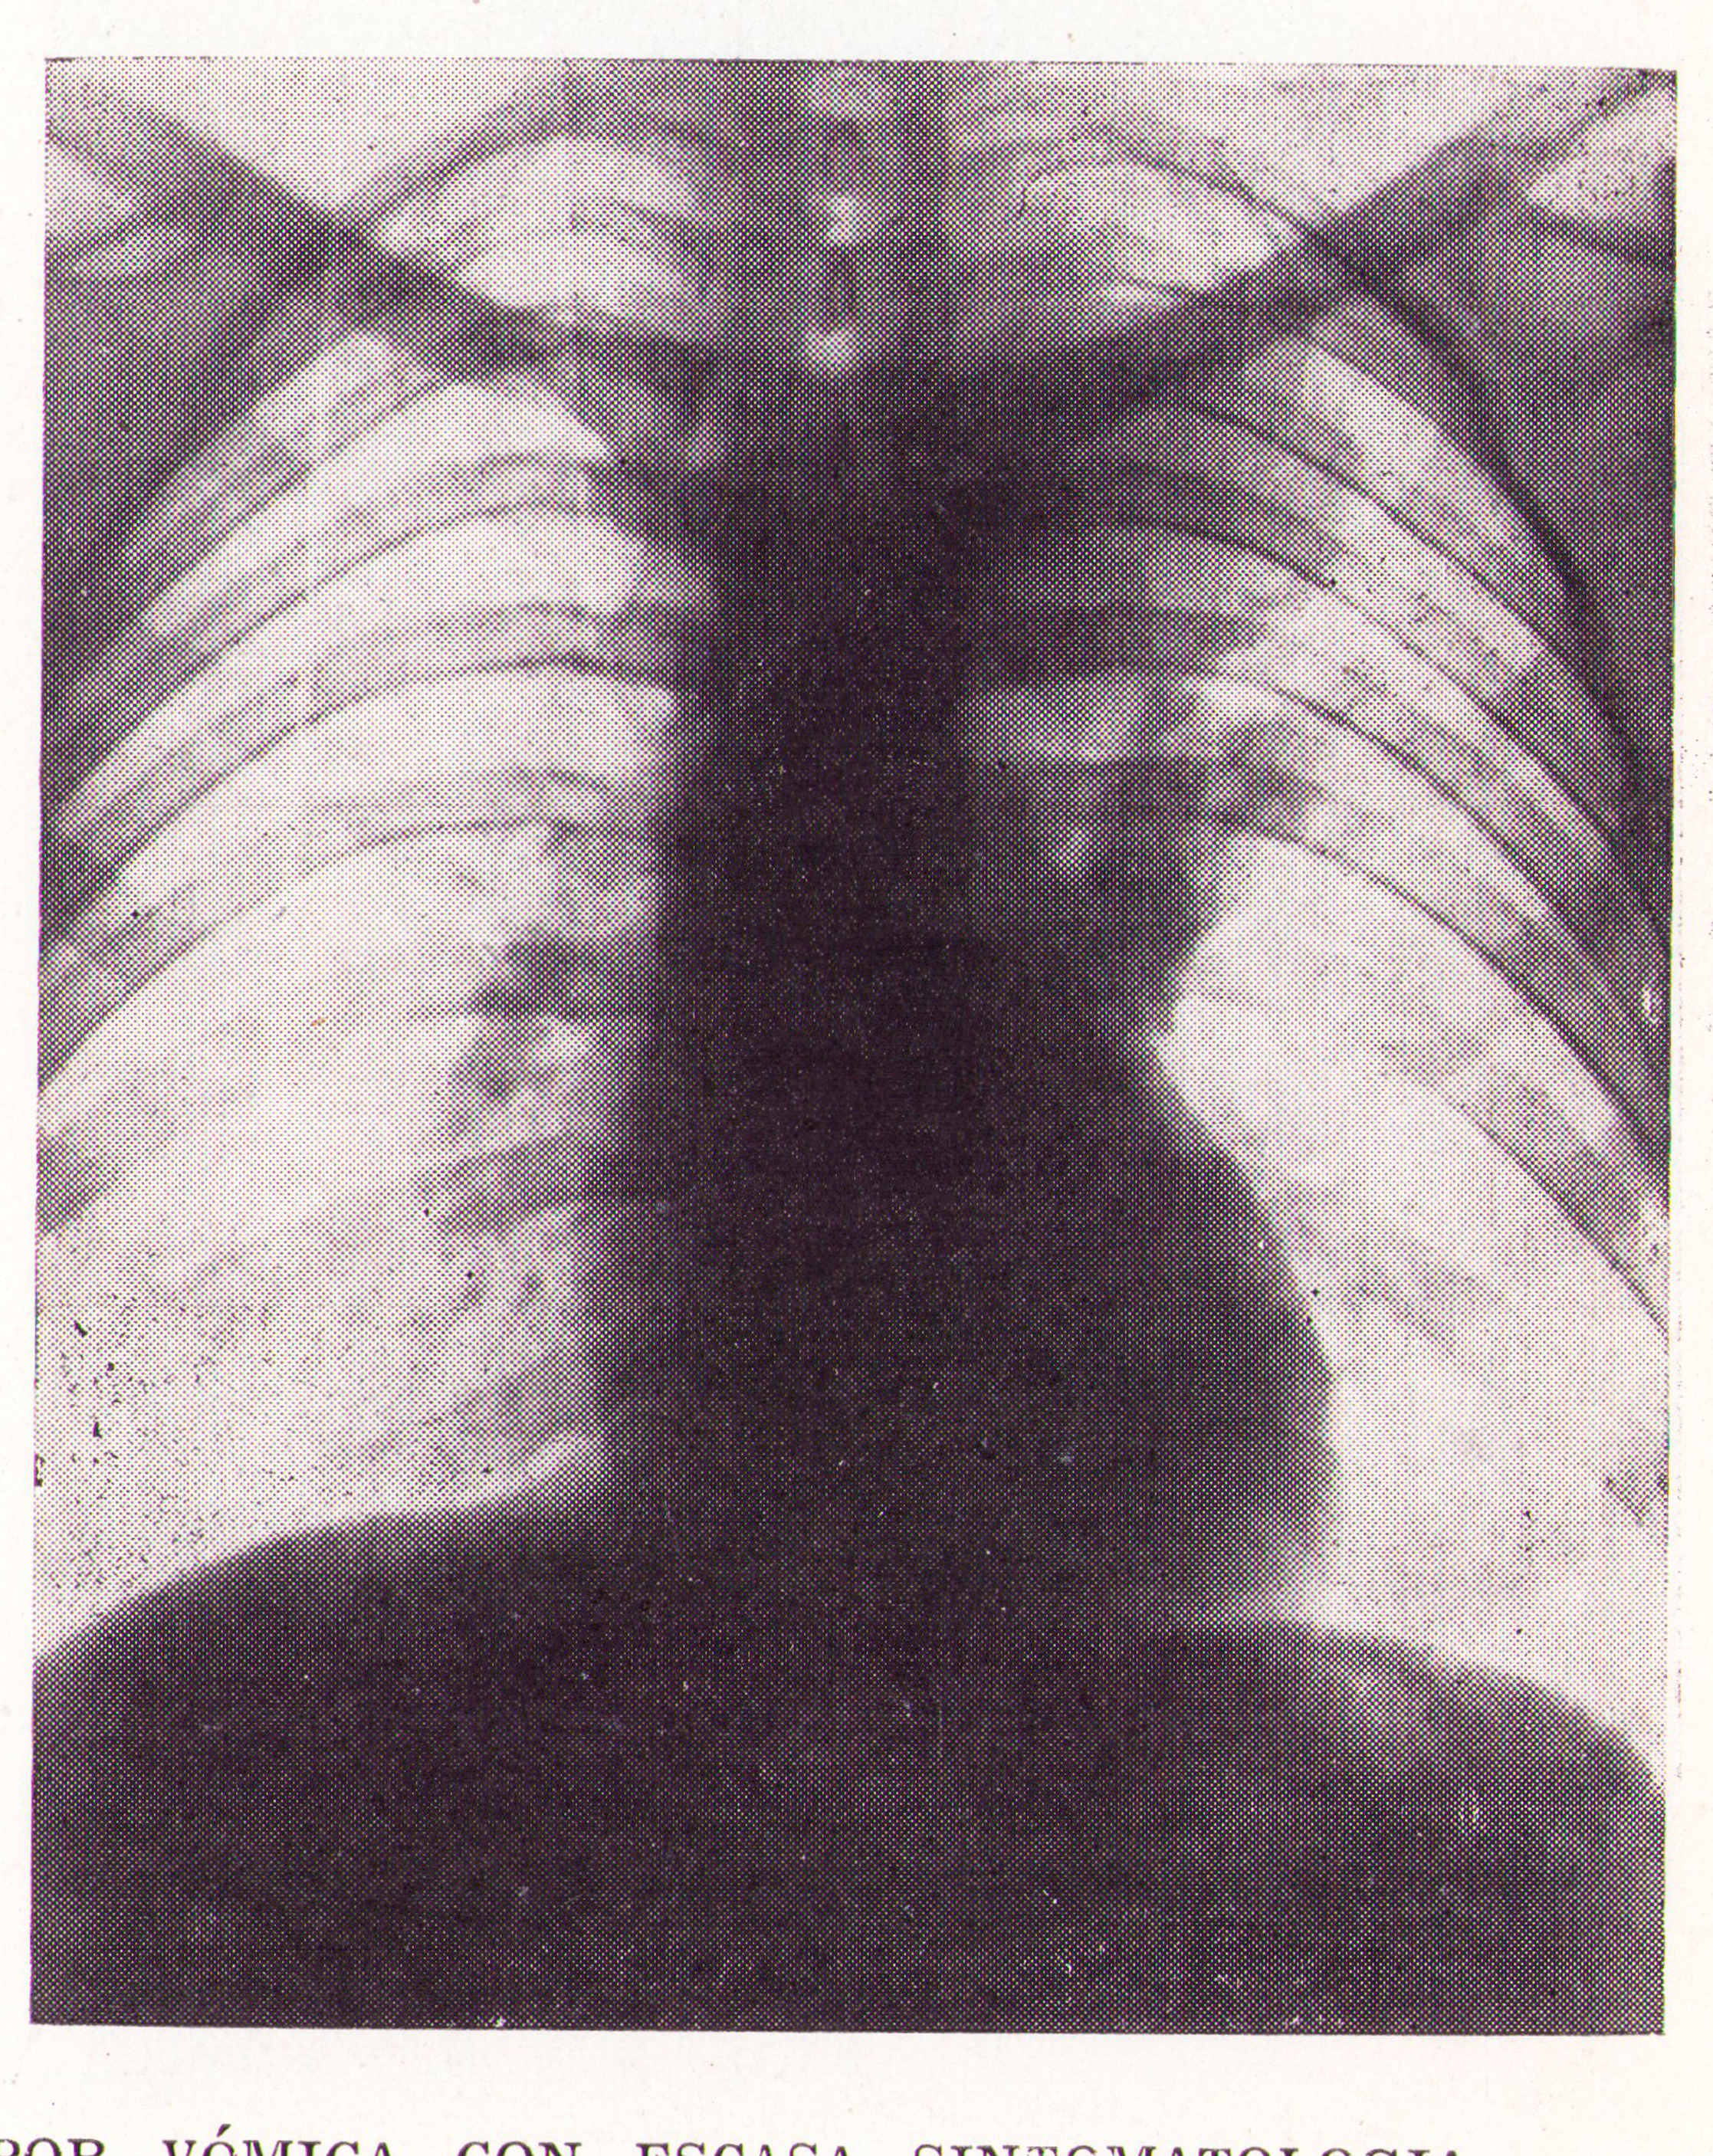

Quistes evacuado por vómica inapercepta

Fig.4. Revista Española de ciencias médicas, Clínica y laboratorio, 1953.